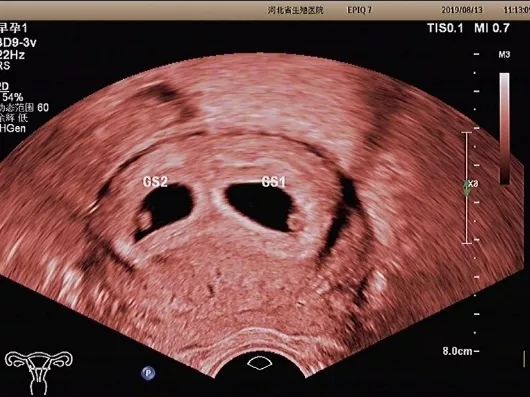

妊娠囊

确定妊娠囊是否在宫腔内,妊娠囊在宫腔内的位置、数目及大小。妊娠囊的大小可随孕周增长而增长。